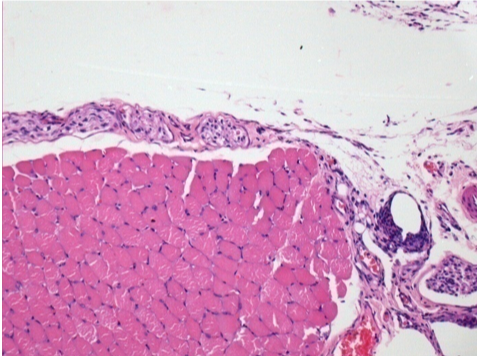

1 mes después de la inyección de Endopeel 0,1 ml en el músculo pretibial derecho.

¡Lo que se ve en negro en las imágenes no es una necrosis como podrían imaginar algunos científicos!

De hecho, hay que tener en cuenta 4 conclusiones